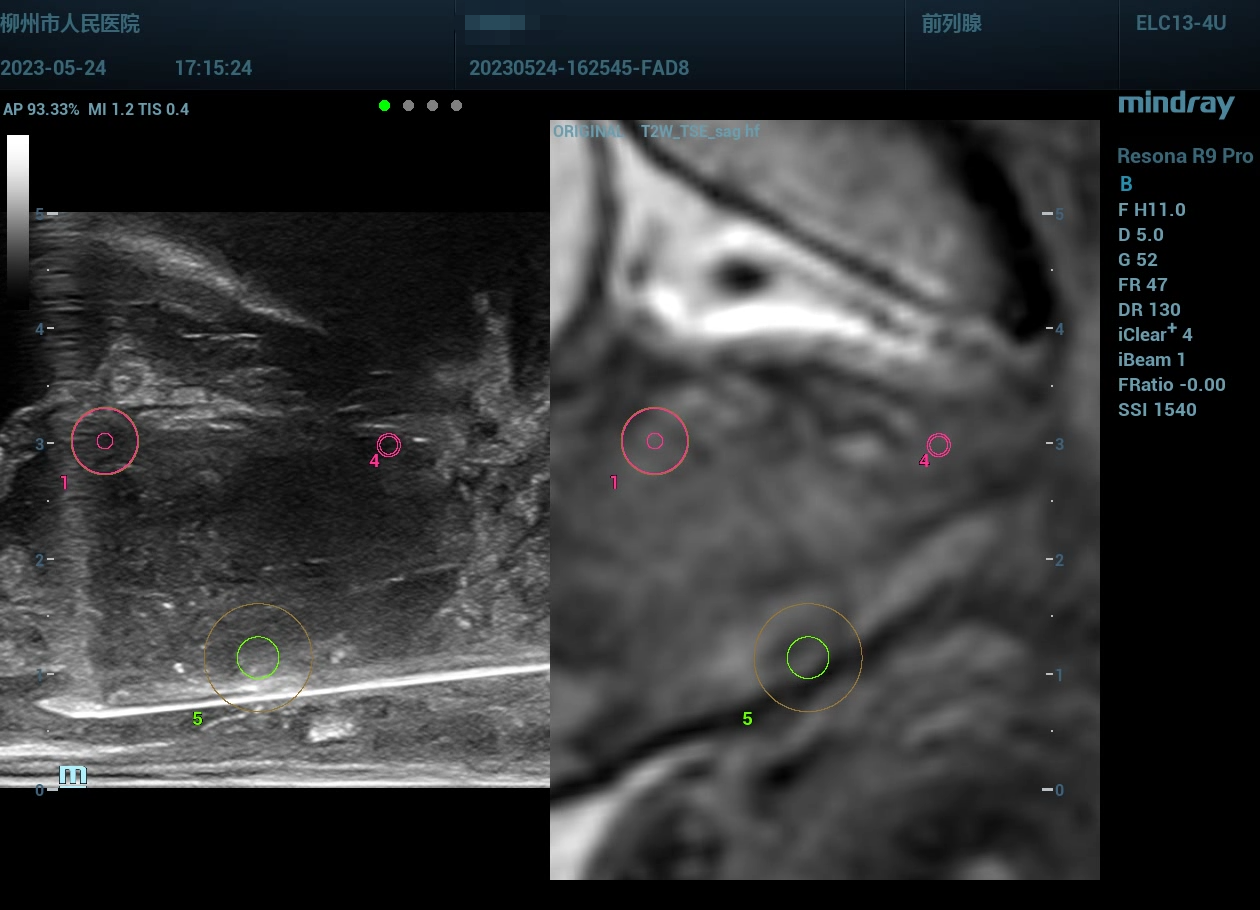

Q8:认知融合 VS 软件融合?

多模态影像(多模式TRUS+mp-MRI )的靶向前列腺穿刺活检术在发现有临床意义前列腺癌、避免过度诊断方面具有明显的优势。

image.png

1686649675457.jpg

1686649503154.jpg